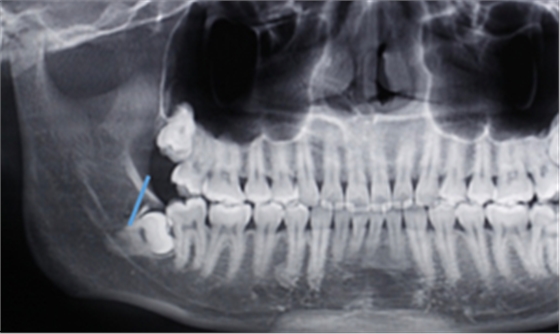

第二:充分暴露牙體組織后,沿47牙長軸方向?qū)?8進(jìn)行分冠,分冠線如下:

第三:分冠后近中牙體組織若無法順利脫位,可進(jìn)一步將近中牙冠分為頰舌兩部分,依次脫位。